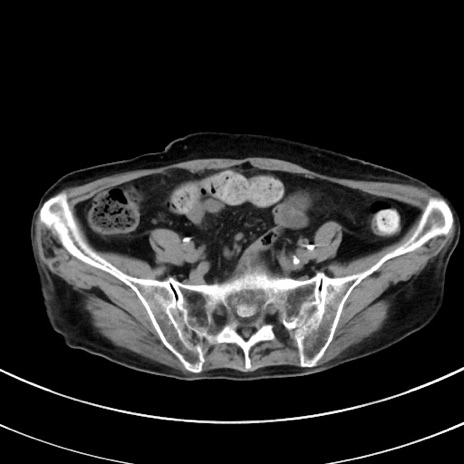

症例33(横断像)

【症例】70歳代 女性

【主訴】心窩部痛

【現病歴】延髄病変の精査・加療にて神経内科入院中。本日より心窩部痛あり。

【既往歴】虫垂炎

【身体所見】右下腹部を中心に圧痛と反跳痛あり。

【データ】WBC 10900、CRP 0.02